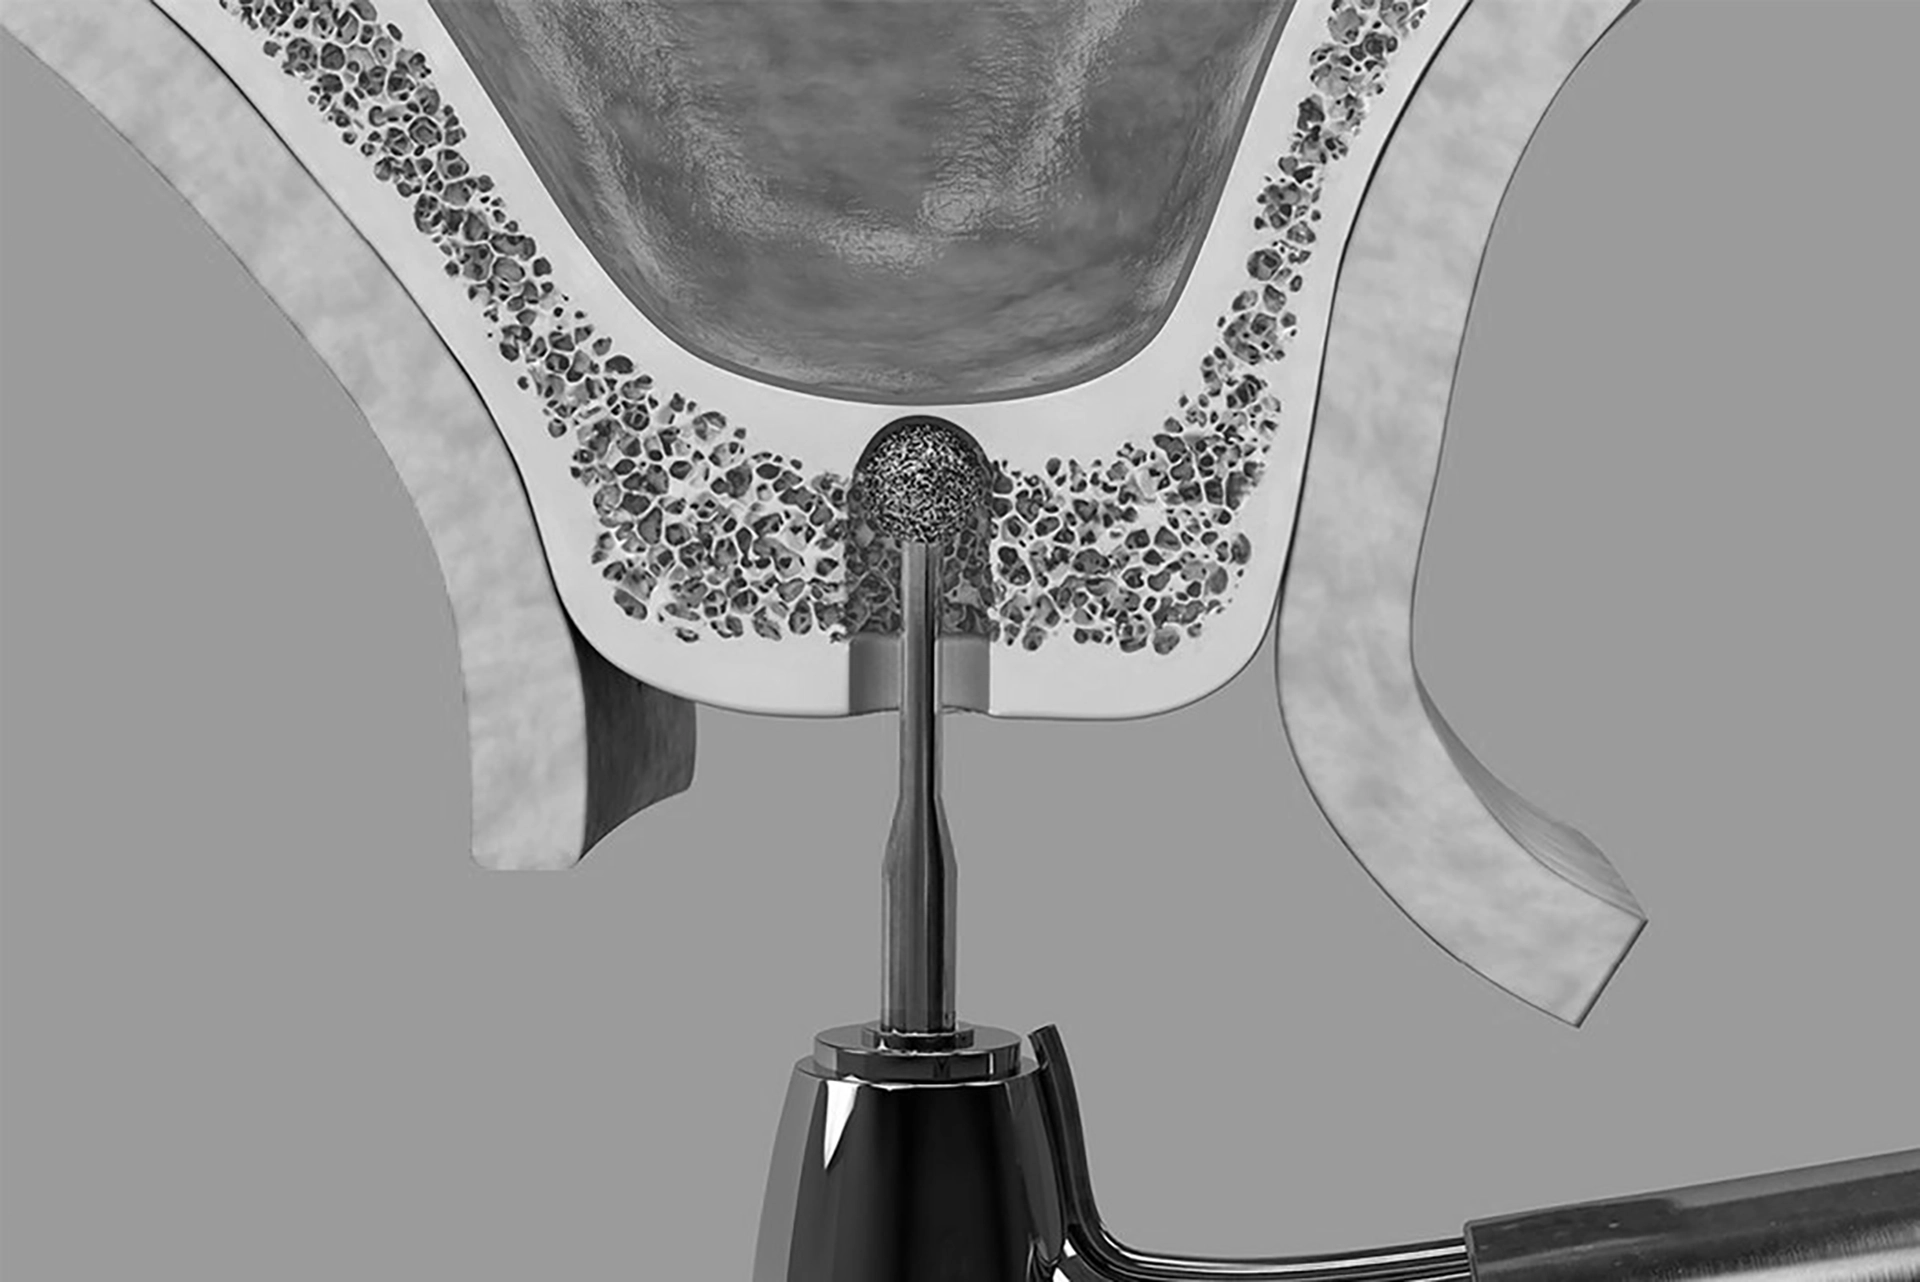

Accessing the Sinus

The gum is carefully opened to expose the underlying bone. A small opening drills into the bone to reach the maxillary sinus cavity.

Lifting the Sinus Lining

The sinus lining is gently lifted away, creating a space below the sinus floor.

Bone Graft Placement

The newly created space is filled with bone graft material, which is typically animal-derived or synthetic.